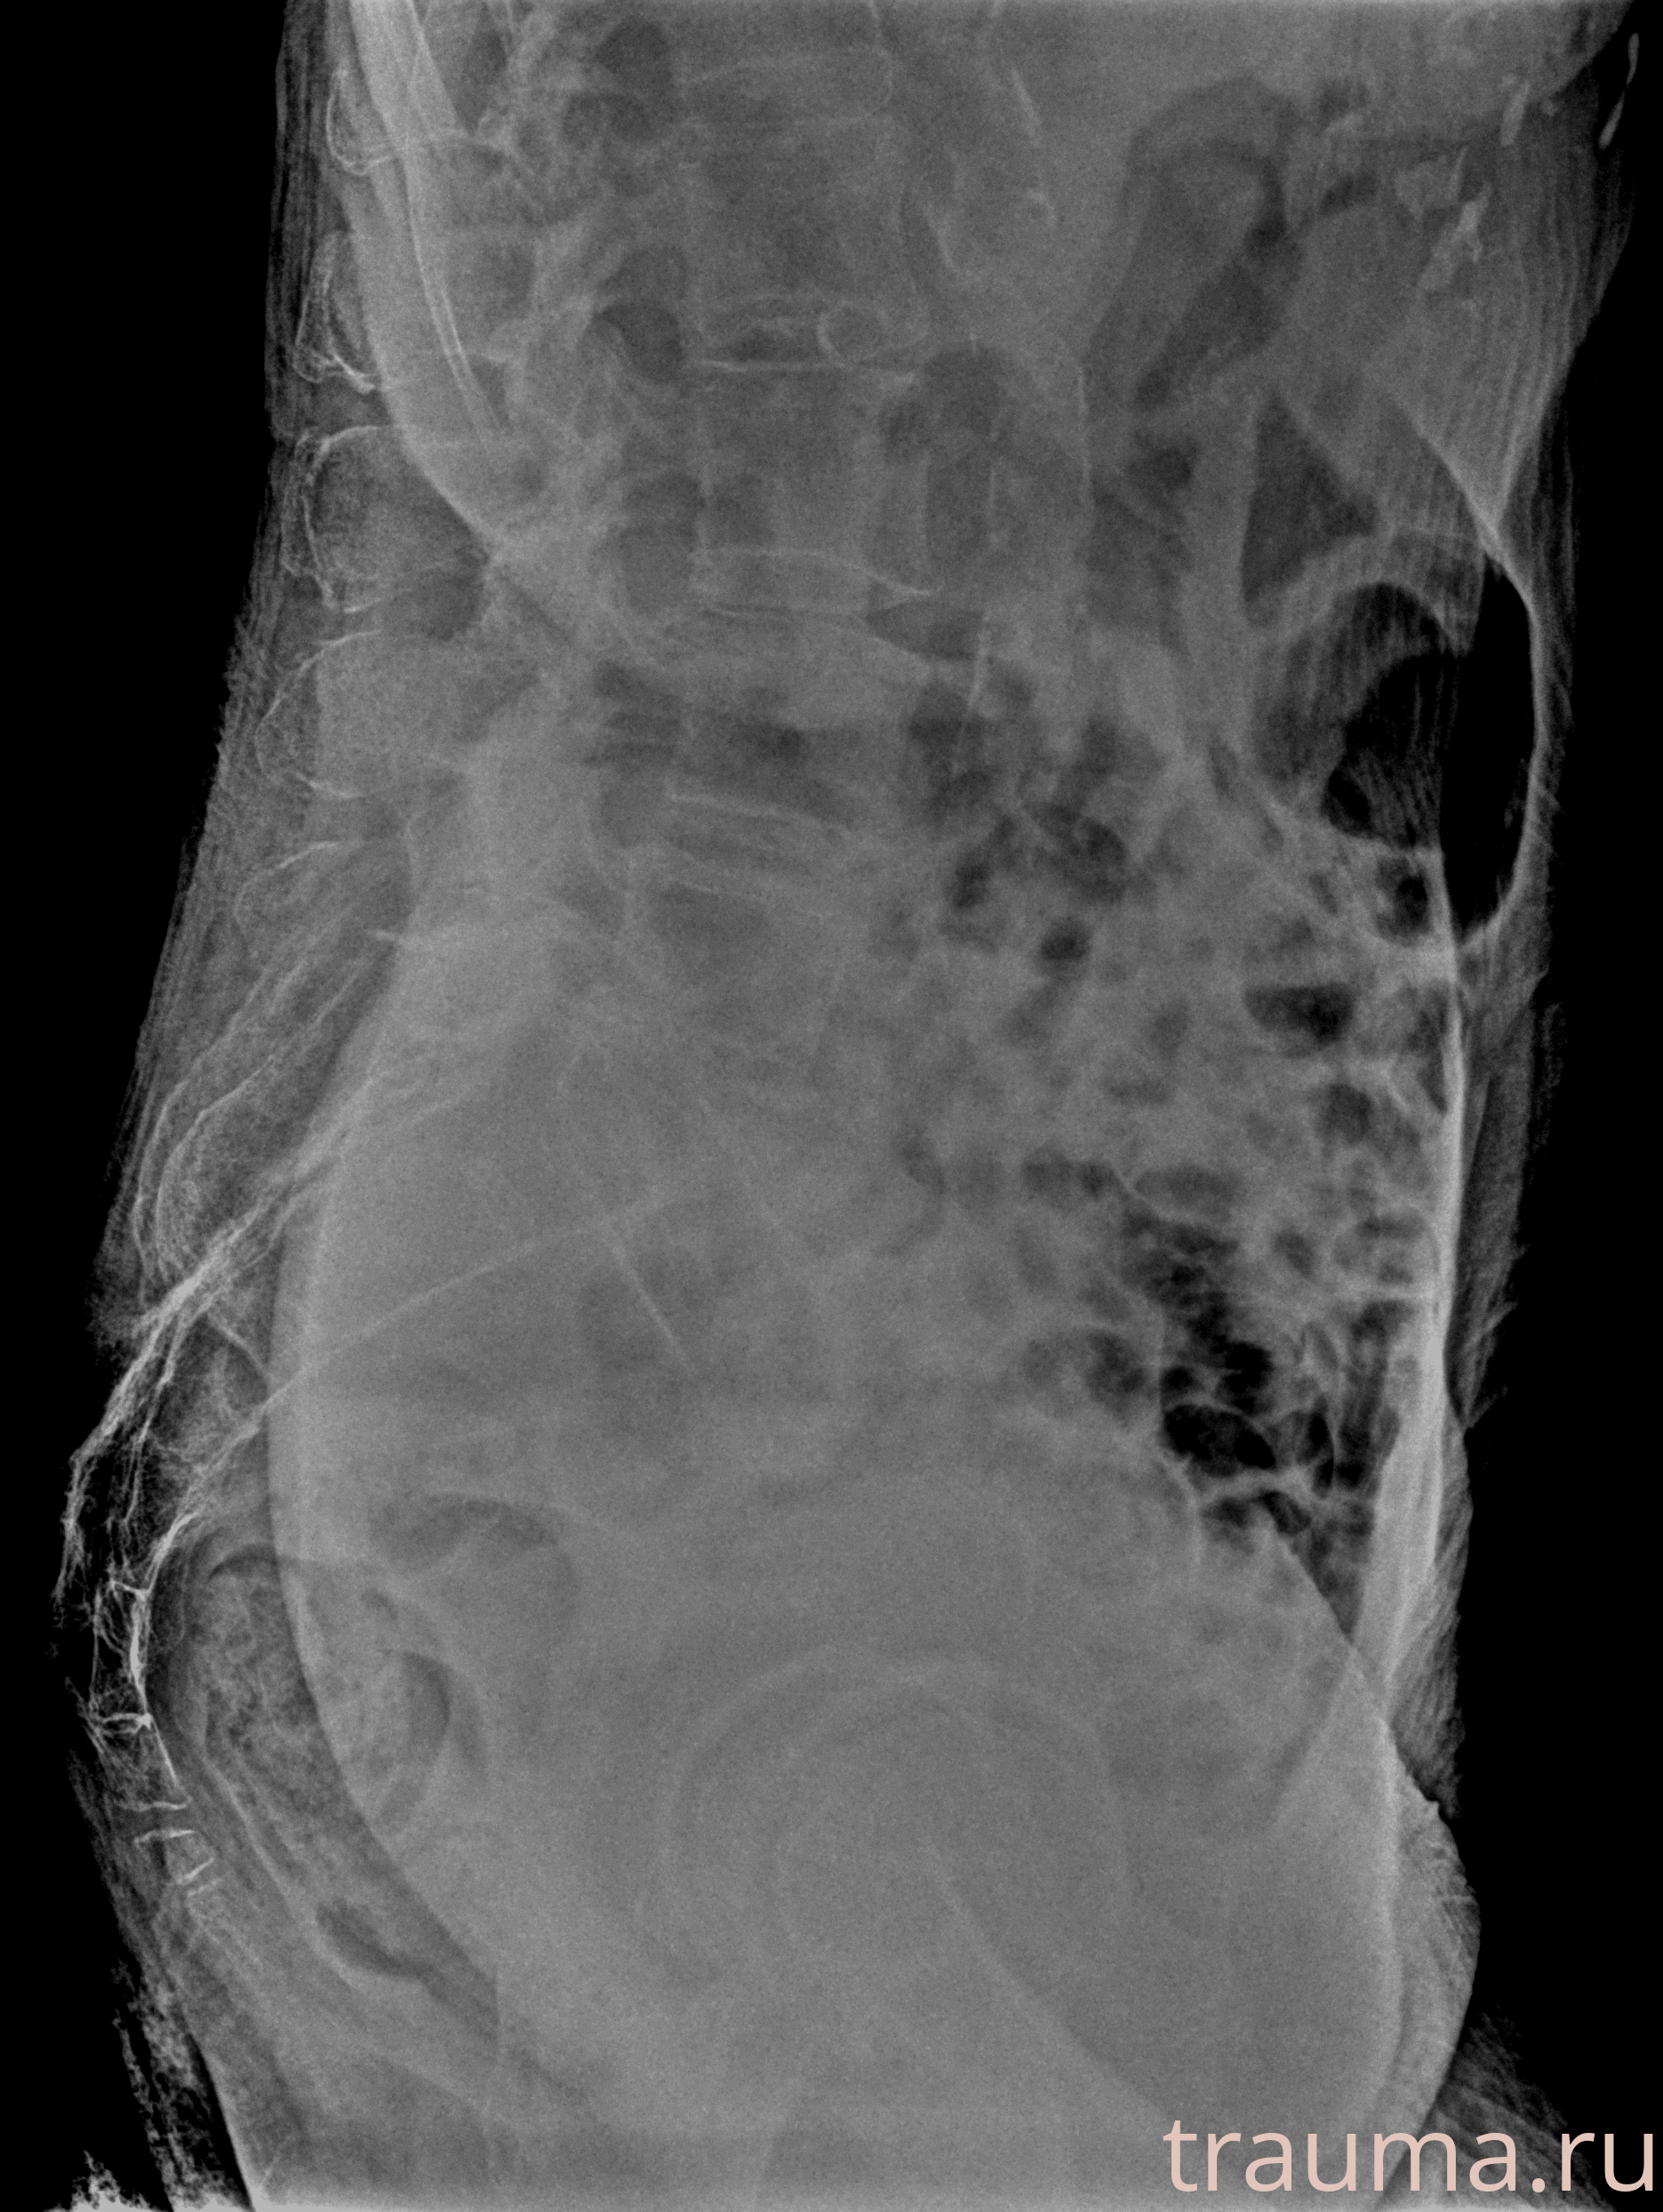

Рентгенограммы

Рентген на дому: по вашему адресу приезжает врач-рентгенолог, травматолог-ортопед с мобильным рентгеновским аппаратом, проводит диагностику травмы или заболевания, делает необходимые рентгенограммы, дает рекомендации по дальнейшему лечению. Получить качественные снимки в домашних условиях возможно благодаря уникальной методике, разработанной МосРентген Центром для института  Склифосовского

при переломе шейки бедра и пневмонии от компании МосРентген Центр - партнера Института имени Склифосовского